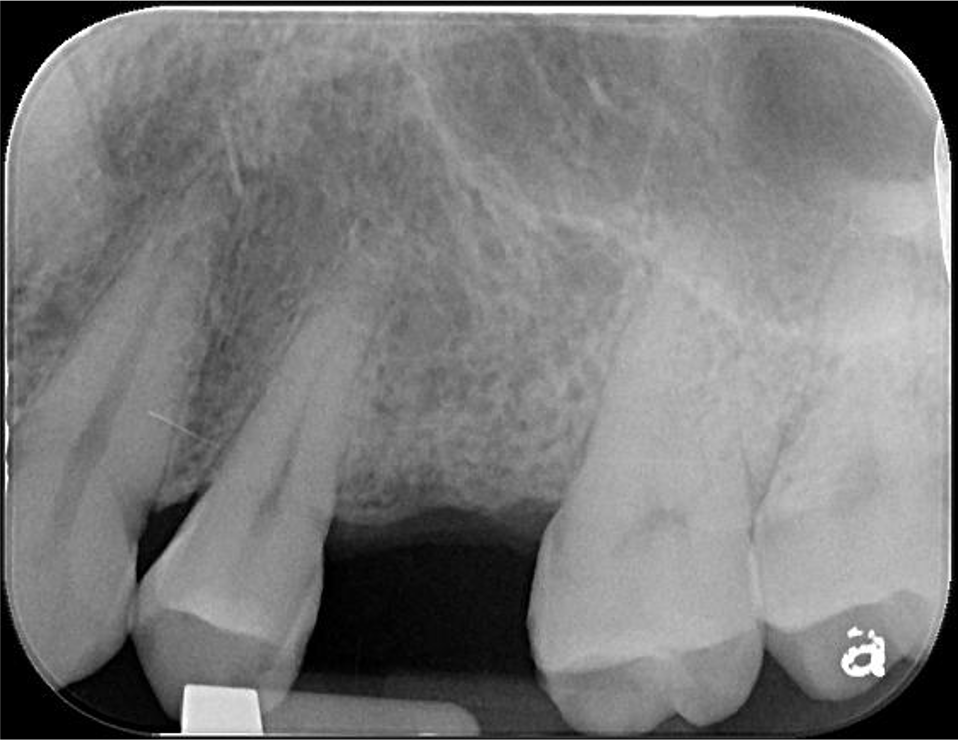

植牙位電腦斷評估